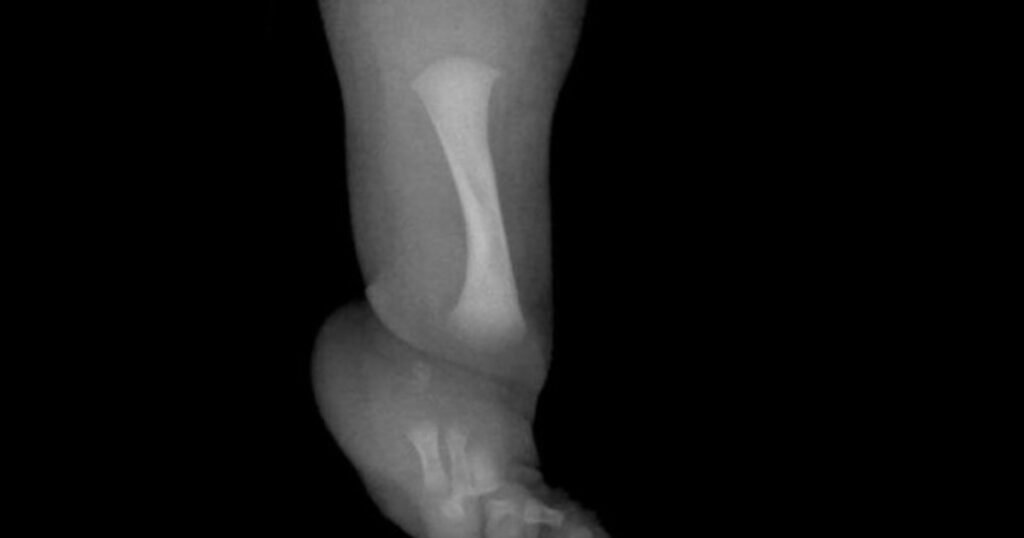

Un nene con una rara enfermedad fue operado para desarrollar un hueso fundamental

Un niño de nueve años se ha sometido en el Reino Unido a una cirugía pionera.Es para menores que tengan hemimelia fibular.